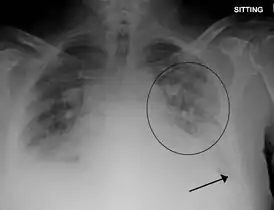

Рентгенография: линии Керли при застойной сердечной недостаточности с интерстициальным отёком лёгких, симптом «крыльев бабочки» или диффузные очагово-сливные изменения при альвеолярном отёке.